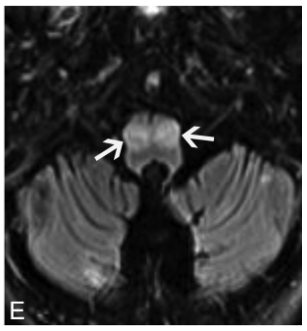

画像所見は,病期によって画像所見が異なる.

急性期は小脳や小脳脚,脳幹部のT2高信号and/or造影効果を呈する.

進行すると(慢性期),小脳や脳幹部が萎縮することがある.Waller変性を生じると橋の十字型T2高信号や中小脳脚のT2高信号を生じ,多系統萎縮症(MSA)と非常に類似した画像となりうる.

オリーブ核の異常肥大性変性(Hypertrophic olivary degeneration)が見られることがあり,歯状核ルイ体オリーブ経路が障害されるためと考えられる.